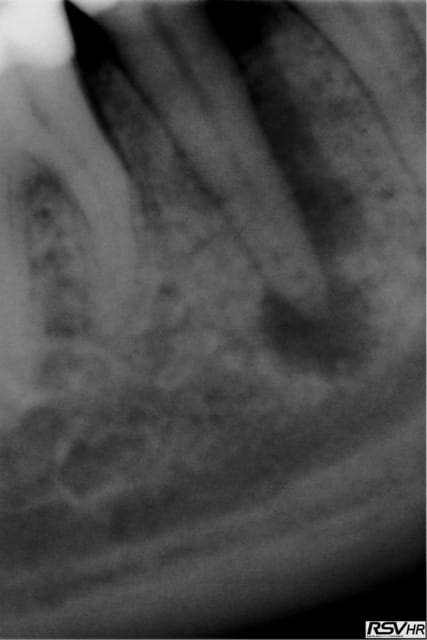

je joins un cas de traitement sur 45 ;nécrobiose,digue,hypo

1 instrument acier en cathétérisme,séquence NITI héroshaper

20%à6% puis4% 25à4% 30à4%,sealite regular,1 cône gutta fine-médium,1 compactage avec thermocompacteur(traitement

sous A.B car risques de douleurs par reprise bactérienne

Chances: des canaux secondaires obturés par le ciment

guérison de l'apex pas de douleurs pendant le compactage

cône de gutta avec "tug back" légère sensation d'échauffement

pas de douleurs post-opératoires

Un rêve....(sauf pas de HN;reconstitution SC33;sauvé par la CCM)!